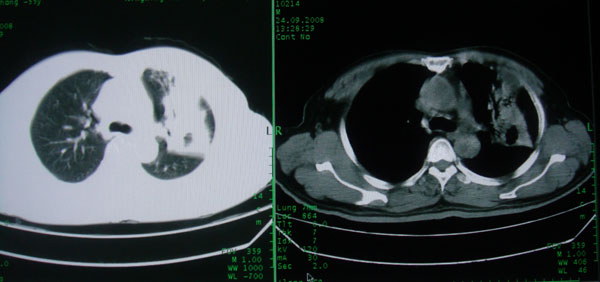

患者男性58岁因二周前起咳嗽,今天胸片示左上肺占位性病变行ct检查,无发热,无咯血痰.

左上肺感染性病变,结核伴空洞形成可能,左上肺膨胀不全

左肺上叶病灶,实变但见含气支气管、空洞但未见壁内结节及积液;

考虑:①感染性病变(包括特殊感染型肺tb)

②肿瘤性病变(考虑患者年龄比较大的关系/所以不排除)

初学者。。。左肺空洞性病变,并可见阻塞性肺不张改变,鉴于患者为老年男性,且临床症状仅有咳嗽,全身中毒症状不明显,所以我首先考虑为左肺癌性空洞并左侧肺门淋巴结转移伴左肺阻塞性肺不张。结核性空洞放于第二位考虑,可以进行相关实验室检查。希望能有病理结果,谢谢!!!!!

左肺上叶实变影,内见支气管充气征及空洞影,病人年龄较大,无发热及结核中毒症状,心影左移,未见纵隔淋巴结肿大;不知实验室检查结果如何?有否嗜酸细胞增多,有没有进行治疗?就目前资料首先考虑1.感染性病变,2.慢性嗜酸性肺炎?可结合实验室检查并短期治疗复查,肺癌不能排除。